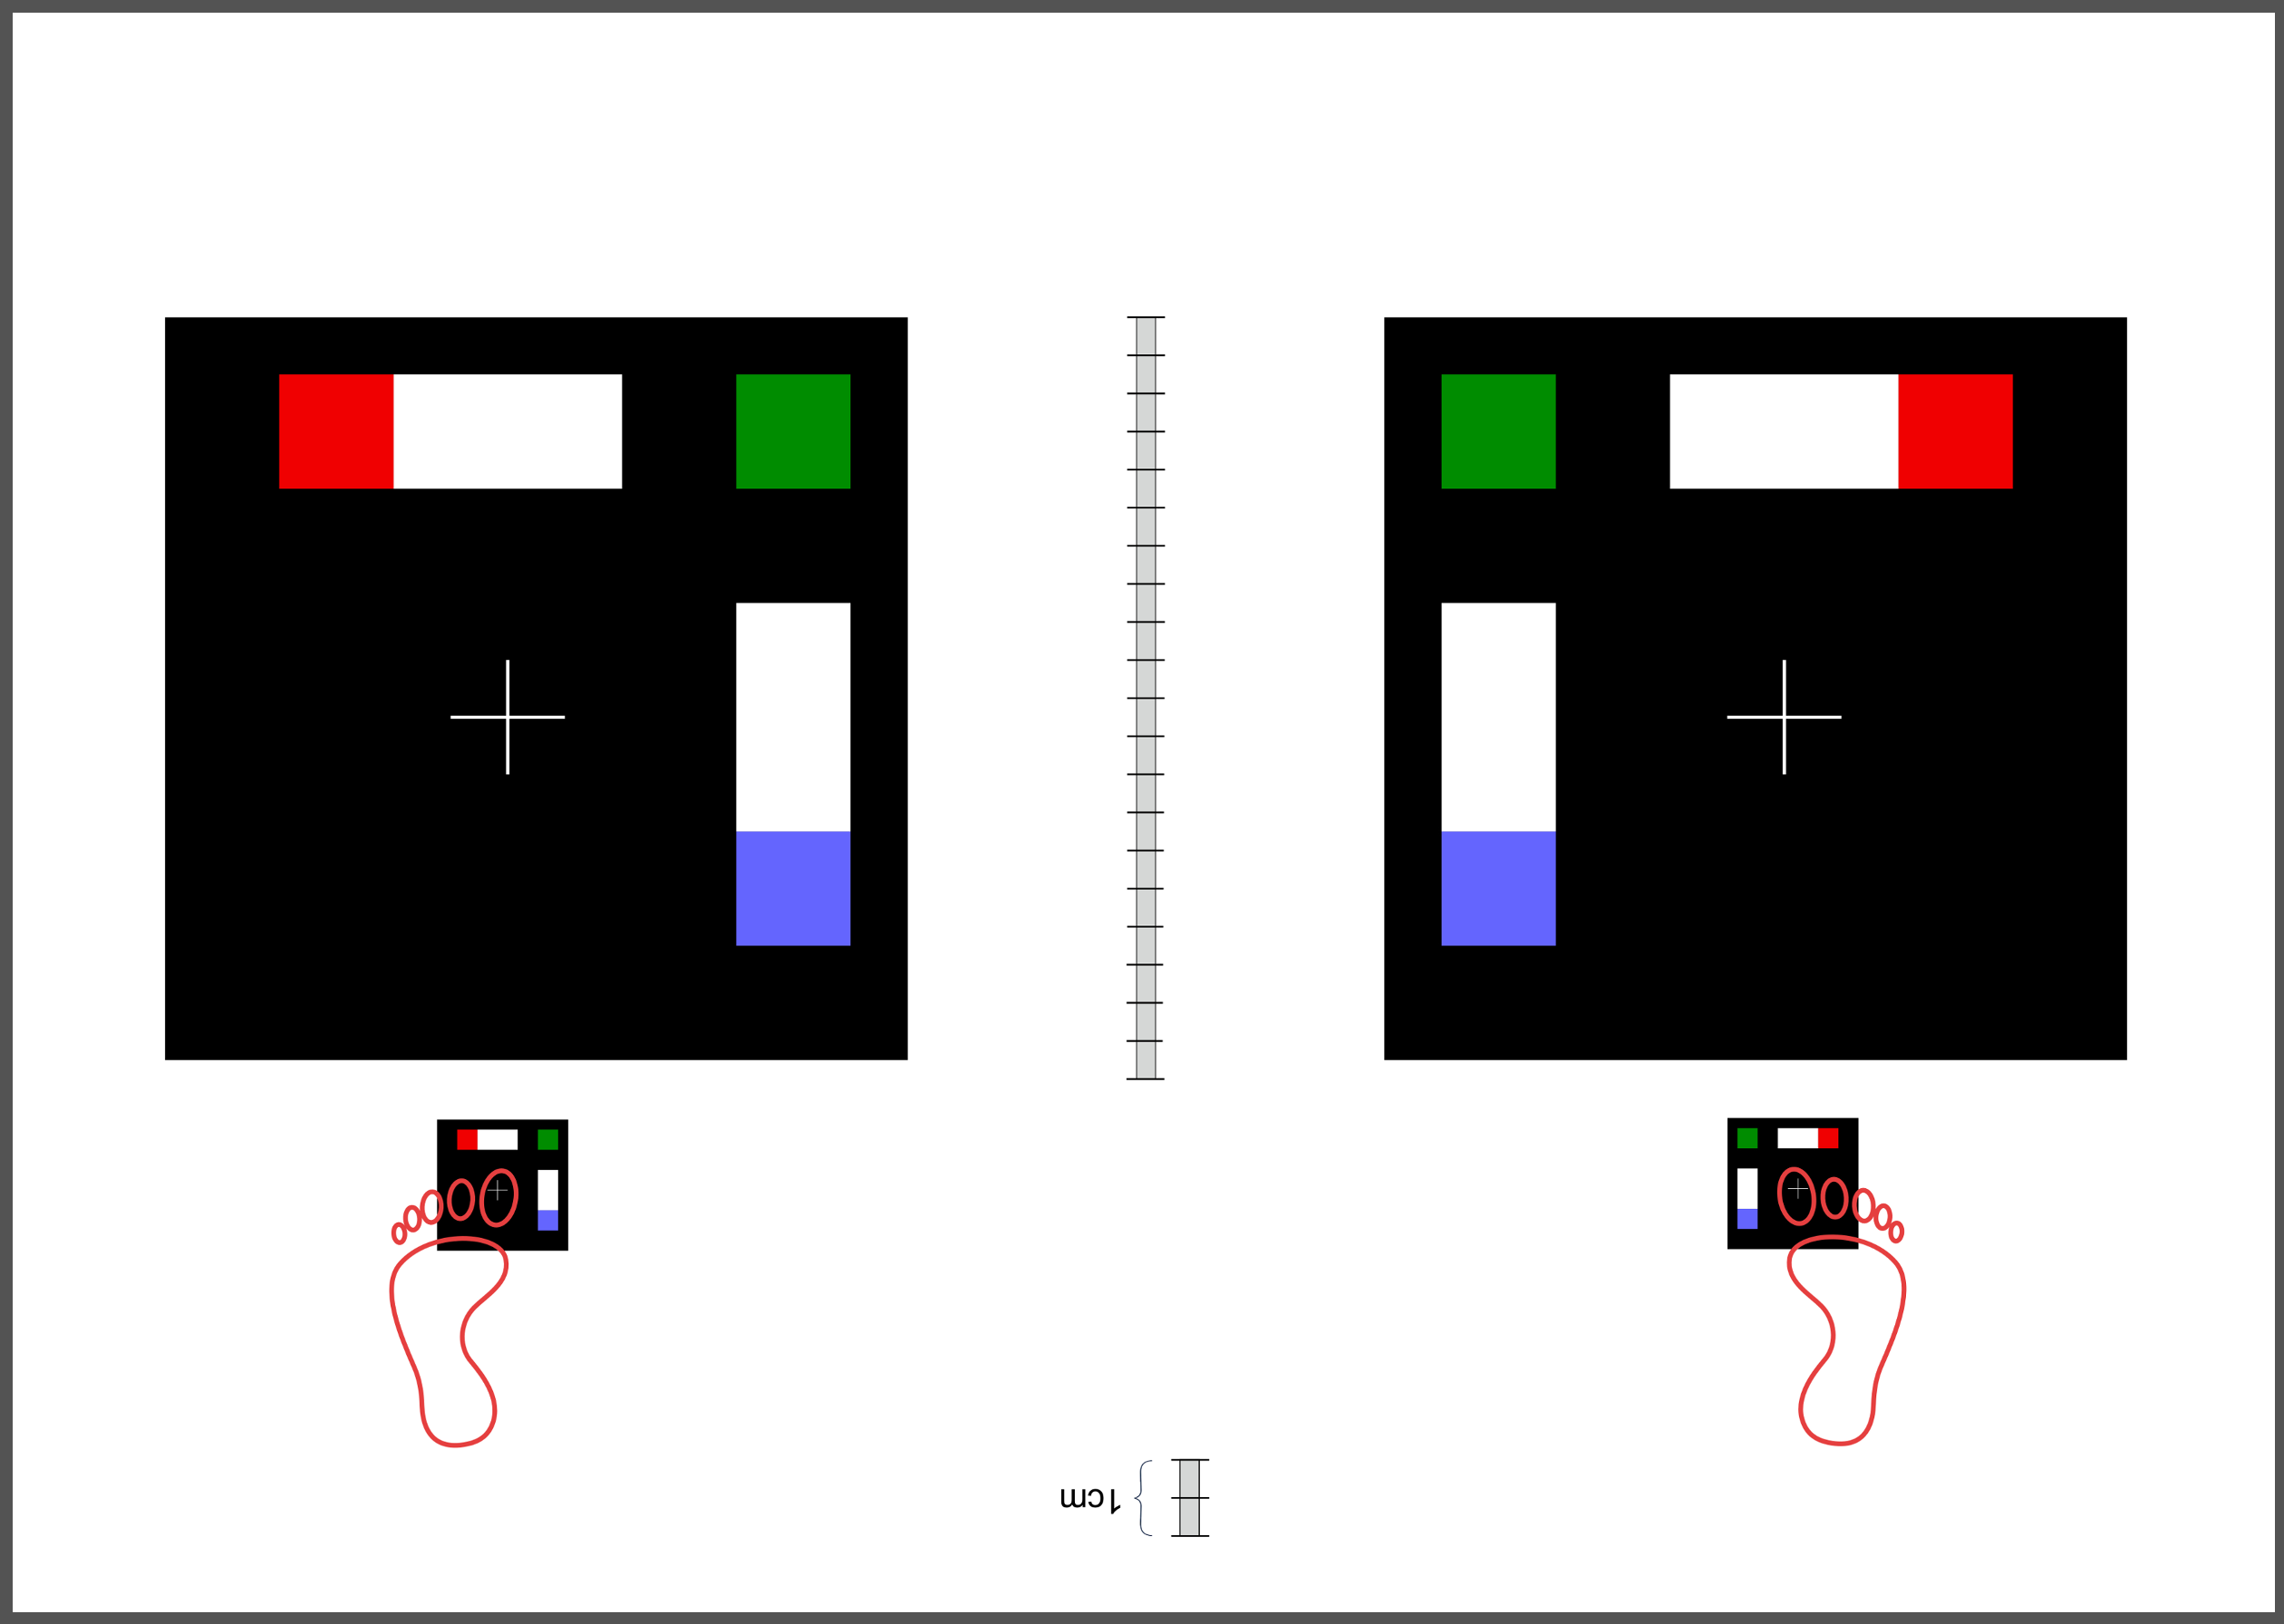

The dataset used in this study was taken in the clinical practice. Following the guidelines of a well-defined medical study, images were acquired in real conditions. All of them were captured in the doctor’s office with their smartphones’ embedded camera. To control some of the environmental conditions, we designed a template to use as the scene background (see Figure 2). During the acquisition process, however, we could not control some other environmental conditions, such as the capture viewpoint the camera setup or the illumination.

Before tackling the image segmentation problem, we perform an image normalization process based on the template’s known measures. It consists on transforming the input image, as seen in Fig. 3 (left), to an image with standard dimensions and orientation, Fig. 3 (right). To achieve our objective we detect the position of the template corners and geometrically transform the image with an affine mapping. As a result, all normalized images appear to had been taken under the same point of view. We remark that the three template colored squares are mapped to the top-right, bottom-right and bottom-left image corners. In particular, left foot images are mirrored. Normalized images are always set to measure pixels. Since the real region inside the template measures cm, a centimetre in the normalized image accounts for 300 pixels, which can be used to measure distances and areas.

The dataset is composed of 348 images of human big toes acquired using the doctor’s cameras attached to off-the-shelf smartphones. A sample image is found in Fig. 8. As previously explained, during the image acquisition stage, some parameters could not be controlled, such as the illumination, the specific capture viewpoint and the camera specifications.